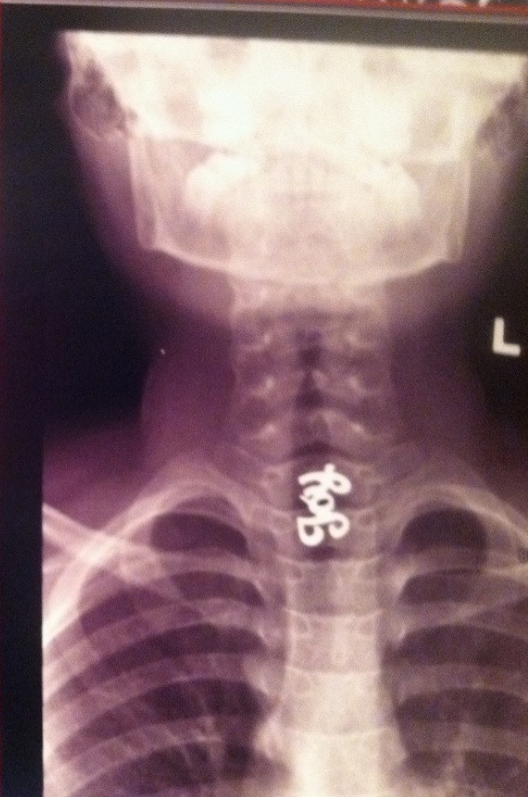

И нет, она не приклеится к кишечнику и не образует огромный «камень» из жвачки. Даже если полностью она не растворится, говорит Ганджу, ее просто вынесет наружу вместе с другими фекальными массами, как, скажем, нераскрывшееся зернышко попкорна. Единственный случай, когда проглатывание жвачки может вас обеспокоить — слишком большой для прохождения через пищевод кусок, но его вам, вероятно, не придет в голову проглатывать, и уж точно его сложно проглотить незаметно!